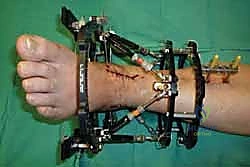

خطوات جراحة تثبيت مفصل الكاحل الأمامي بالتفصيل (Step-by-Step Surgical Procedure)

تُجرى العملية تحت التخدير العام أو النصفي (الشوكي)، وتستغرق عادةً بين ساعتين إلى ثلاث ساعات، وتتطلب دقة ومهارة فائقتين. إليكم الخطوات الجراحية كما ينفذها الأستاذ الدكتور محمد هطيف: